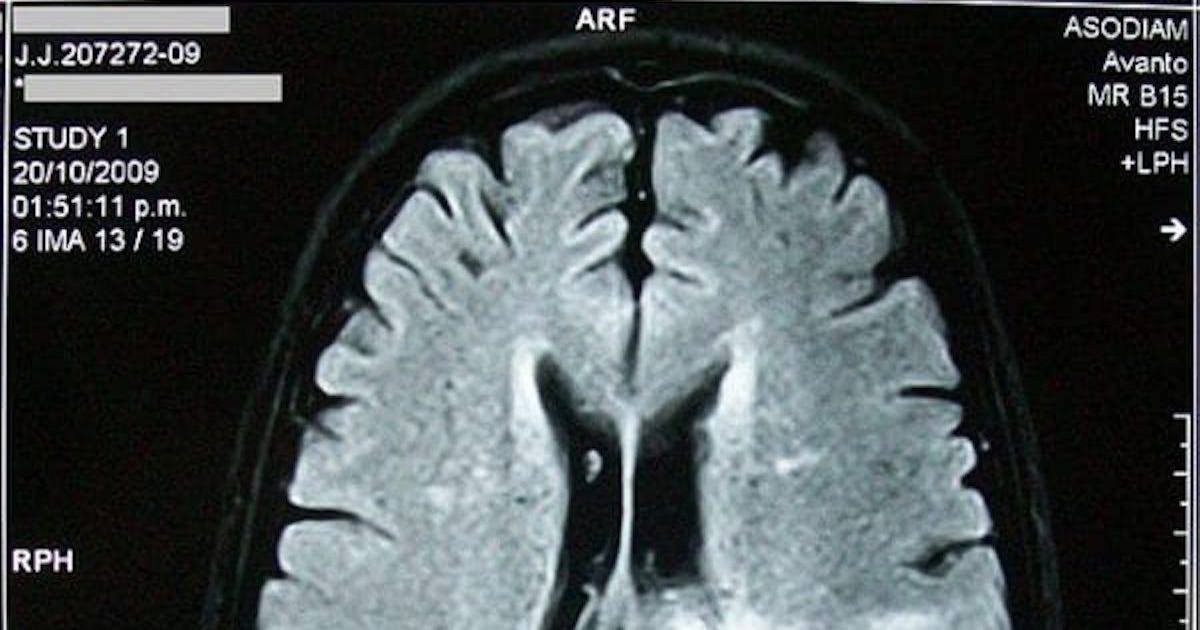

The doctor urged him to go to the hospital “immediately” for an MRI that revealed a mass in his brainstem, a moment that sent a wave of fear through both him and his mother, Sonora Swords.

With neurosurgical resources limited in Sioux City, Jones was transferred to Mercy Hospital, where another MRI was performed and surgery was initially discussed. However, uncertainty about the tumor’s location and its delicate position near the brainstem led doctors to refer him to a facility in Omaha for more advanced imaging.

“And then that’s when they told me that there was a 2-centimeter tumor inside of my brain stem,” said Jones. “It had fused to my brainstem walls.”

Despite the challenges, the biopsy confirmed that Jones had diffuse midline glioma (DMG), a rare and aggressive brain cancer known for its resistance to treatment, and that cannot be separated from the surrounding tissue.